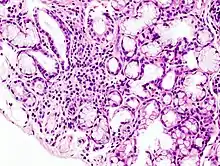

| Image with a microscope of focal lymphoid infiltration in the minor salivary gland associated with Sjögren's syndrome. | |